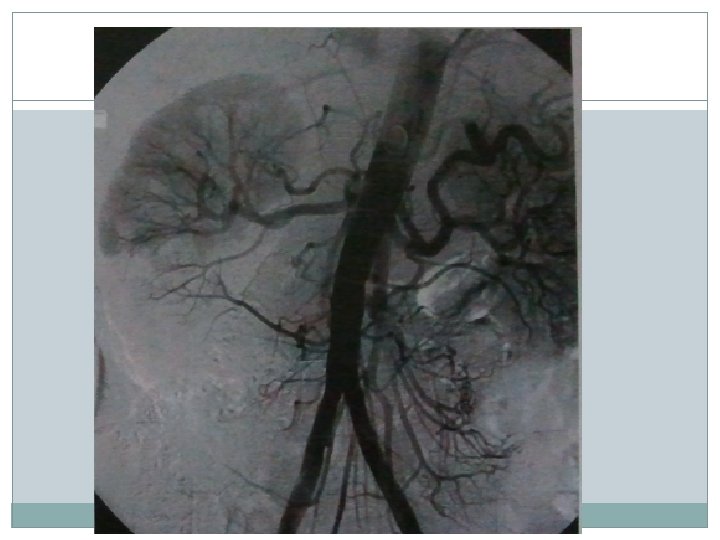

Artérias Renais �As artérias renais saem ao nível de L 1 -L 2 �Artéria renal acessória (25%) origina em qualquer lugar da aorta suprarenal ou artérias ilíacas �Arteriografia renal: - Punção femoral - Punção braquial se angulação extremamente cranial ou aneurisma/ateromatose infrarenal - 1° estágio: aortograma abdominal, permitindo a localização do óstio, angulação da artéria renal e identificação de artéria renal acessória (25%). Feito com cateter 5 F pigtail ao nível de L 1 -L 2, 30 ml à 15 ml/seg

� 2° estágio: cateterização seletiva de artérias renais com 5 F de mamária, hockey stick ou renal doublecurve. Se angulação cranial do óstio, no acesso braquial, pode-se usar o MP. - A injeção de 5 ml/seg 5 -8 ml, devendo ser incluída ambas as fases renais (arterial e nefrográfica - Incidências: OAE/OAD, em doença envolvendo bifurcação requer angulação cranial ou caudal